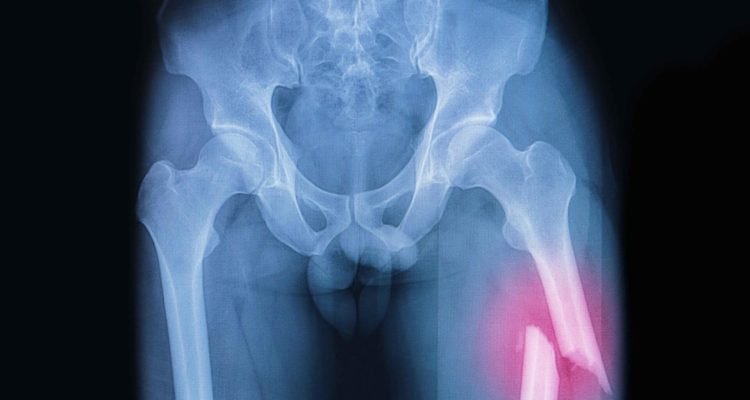

Tuo pačiu metodu galima vizualizuoti keterų lūžius ir kaukolinės aortos kalcinozę.

Naujasis tyrimas, kuriame dalyvavo 5365 paaugliai vyrai, rodo, kad kiekvienas iš šių rodiklių yra susijęs su didesne kamieno lūžių ir kitų lūžių rizika.

Tyrėjai nustatė, kad įtraukus abu rodiklius, o ne tik vieną, pagerėja gebėjimas prognozuoti, kuriems vyrams yra didžiausia tikimybė ateityje patirti kamieno lūžį ar kitą lūžį.

„Tiek kaukolės aortos kalcinozę, tiek stuburo kamieno lūžį galima iš karto ir greitai pastebėti standartinėse rentgenogramose arba stuburo šoninio aspekto nuotraukose, ir gali padėti įvertinti lūžių riziką jauniems vyrams, kuriems yra vienas ar abu rizikos veiksniai”, – sakė pagrindinis autorius daktaras Johnas T. Shawsbaughas iš Kalifornijos universiteto Niujorke. Dr. Johnas T. Shawsbaughas iš Minesotos universiteto.